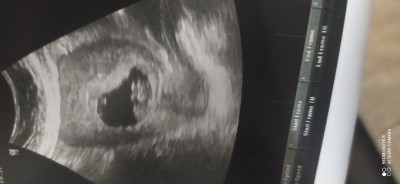

İki farklı zamana ait görüntüler 17 haftalık olduk hala öğrenemedim cinsiyetini bir hafta sonra bakicam tekrar doktor anlayan varsa lütfen yorum yapsın

Gebelik haftası 17